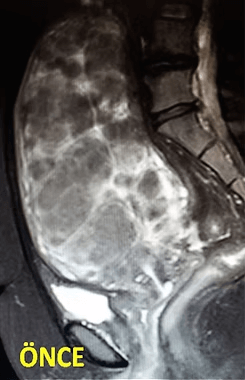

41 yaşında, kabızlık, gaz ve sık idrara çıkma şikayetleri var. Emar’da karını dolduran dev miyom (*) mevcut. Miyomektomi önerilmiş, ancak operasyonda rahimin alınabileceği söylenmiş. Embolizasyondan sonra dev miyomun ve bir başka küçük miyomun öldüğü ve küçüldüğü izleniyor. 7 ay sonra hasta şikayeti kalmamıştır.